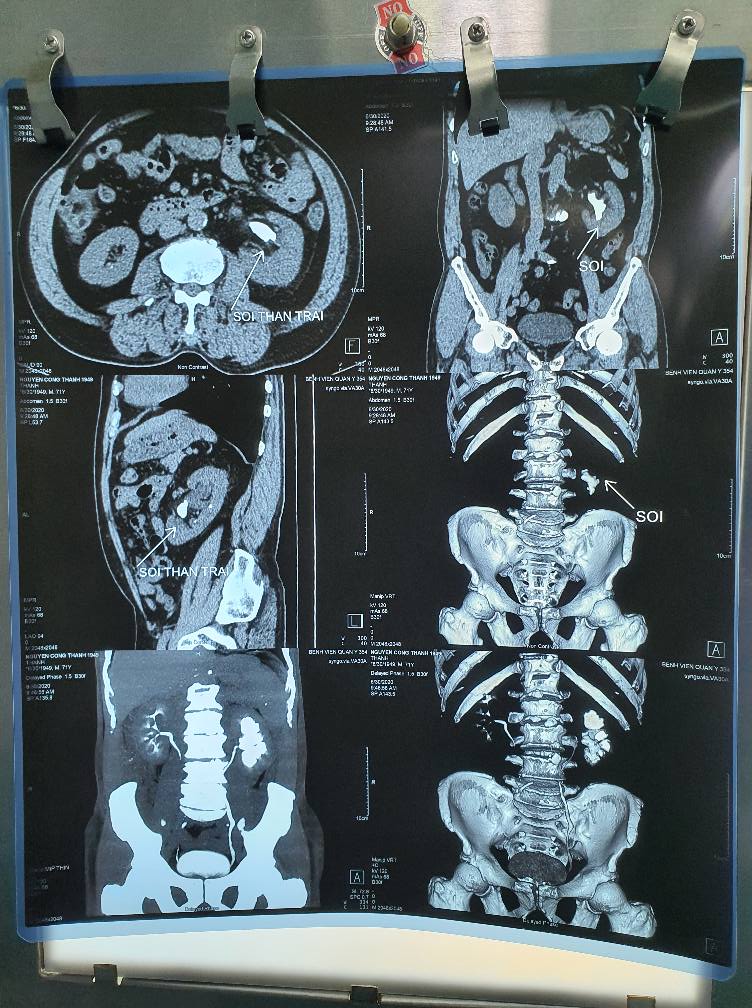

Phẫu thuật được thực hiện nhẹ nhàng, ít gây đau hơn rất nhiều so với mổ mở kinh điển: vì bác sĩ chỉ tạo một vết rạch nhỏ, kích thước 0.5 – 1cm ở vùng lưng để tạo một đường hầm vào đến thận nơi có sỏi, dưới hướng dẫn của siêu âm. Sỏi thận bị tán vụn bằng năng lượng laser. Các mảnh vụn sỏi sẽ được gắp hoặc hút ra ngoài. Khả năng lấy hết sỏi cao, người bệnh nhanh chóng phục hồi sức khỏe.